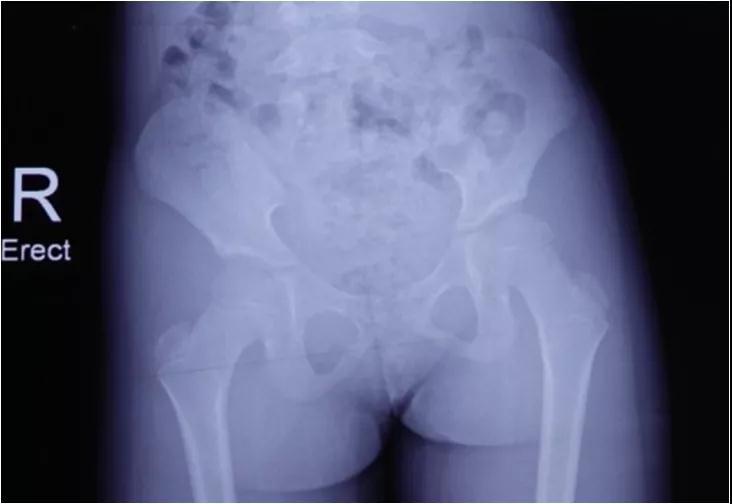

1. 关于拍片,很多家长认为,我回来复查不就是让我拍个片子吗?现在网络这么发达,我在当地拍个片子发微信给你看不就行了吗?殊不知,很多当地医院拍的片子往往是这样子滴!

而我们要求的片子必须是这样子滴。除了单纯的骨盆正位片外,我们要求孩子必须还有一张站立位的下肢全长片。才可以判断,孩子有没有原发的或继发的双下肢不等长。而且,对于髋关节是否还存在某种程度的不稳定,也只有站立位的片子才能够真正表现出来。